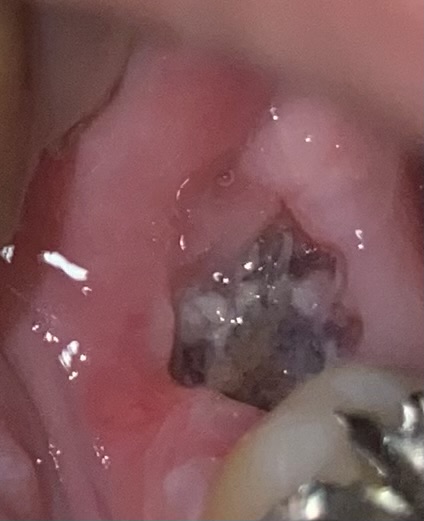

虫歯で抜歯してから1週間経つが、歯茎が柔らかくにおいがします